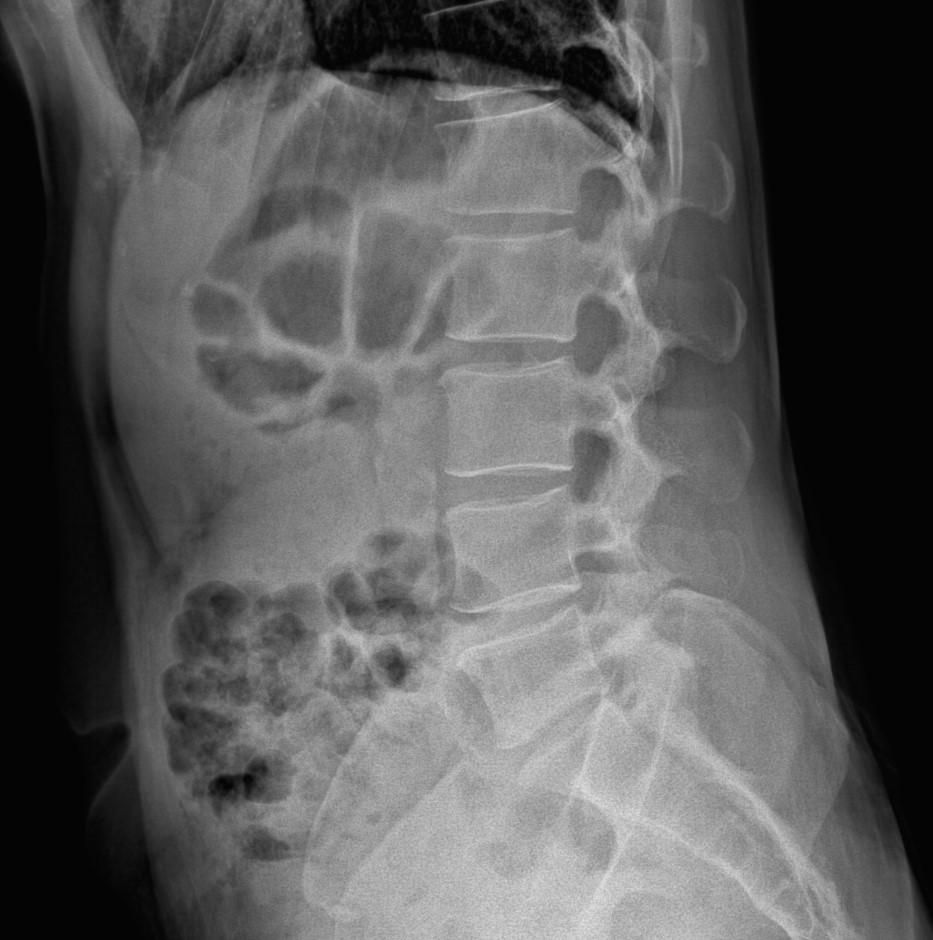

• 4번 째 사진

엑스레이 상에서는 요추 배열이 전반적으로 잘 유지돼 보입니다. 마나 일부 요추 간격이 좁아진 부위가 있어 보입니다. 말씀하신 것처럼 특정 동작에서 찌릿 혹은 뜨끔하거나, 최근 뻐근함이 생기는 건 디스크 초기나 근육, 인대 긴장에서도 나타날 수 있습니다.

허리의 커브가 줄어들어있다는것을 제외하고는 크게 문제가될만한 부분은없는데요 통증과불편감이 지속된다면 MRI와같은 정밀검사가 필요할수있습니다

사진상 요추 사이의 간격이 다소 좁아 보이며 간격이 좁다는 것은 퇴행성 변화를 의미하며 척추의 정렬 또한 큰 전위는 없어 보이나 허리 곡선이 정상보다는 조금 감소한 상태로 이러한 경우 근육의 긴장이나 만성적인 통증이 발생할 수 있습니다.

• 엑스레이 검사를 통해서는 현실적으로 뼈 위주의 평가만 가능하며 정밀하고 자세하게 평가를 내리는 것은 어렵습니다. 올리신 엑스레이 사진들에는 특별히 문제가 있다고 볼만한 소견이 크게 있어보이거나 하지는 않습니다.

우선 현재로썬 척추와 척추 사이인 디스크 공간이 좁지는 않아보이지만 다소 요추의 커브가 감소되어 있어 보입니다.

올려주신 사진에서 크게 특이사항이 보이는 것으로생각되지는 않습니다.

고관절의 구조적인 이상보다는 주변 근육이나 신체기능, 근골격계질환등의 문제로 인해서 통증이 지속될 수 있으므로, 통증이 오래 지속된다면 전문적인 치료를 고려해보시면 좋겠습니다.